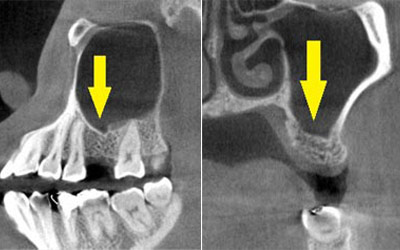

この患者様は、上顎の右前歯が差し歯になっていたのですが、歯の根の先の部分が、腫れを繰り返し、歯根の破折も考えられるとのことで、抜歯して、インプラントかブリッジかと説明されたそうで、インプラント治療を希望されて、当院に相談に来られました。

CTでみると、歯の根の外側の薄い骨がなく、ここに炎症を起こすと、症状の改善は難しい状態でした。抜歯してインプラントということで了承され、抜歯即時インプラント埋入も考えられたのですが、歯の根の状態、骨の状態を考えて、抜歯して、治癒を待ってインプラント埋入をすることとしました。

抜歯して5か月経過後にCT撮影すると、非常に良く治癒していましたが、骨の厚みが4mm程しかありませんでした。そこで、インプラント埋入と同時に外側に人工骨と自家骨を混合して補填し、人工の膜(メンブレン)で覆うという、骨の厚みを造成する手術(GBR)を併用しました。

手術後のCTです。うまくインプラント埋入、骨造成ができていると思います。